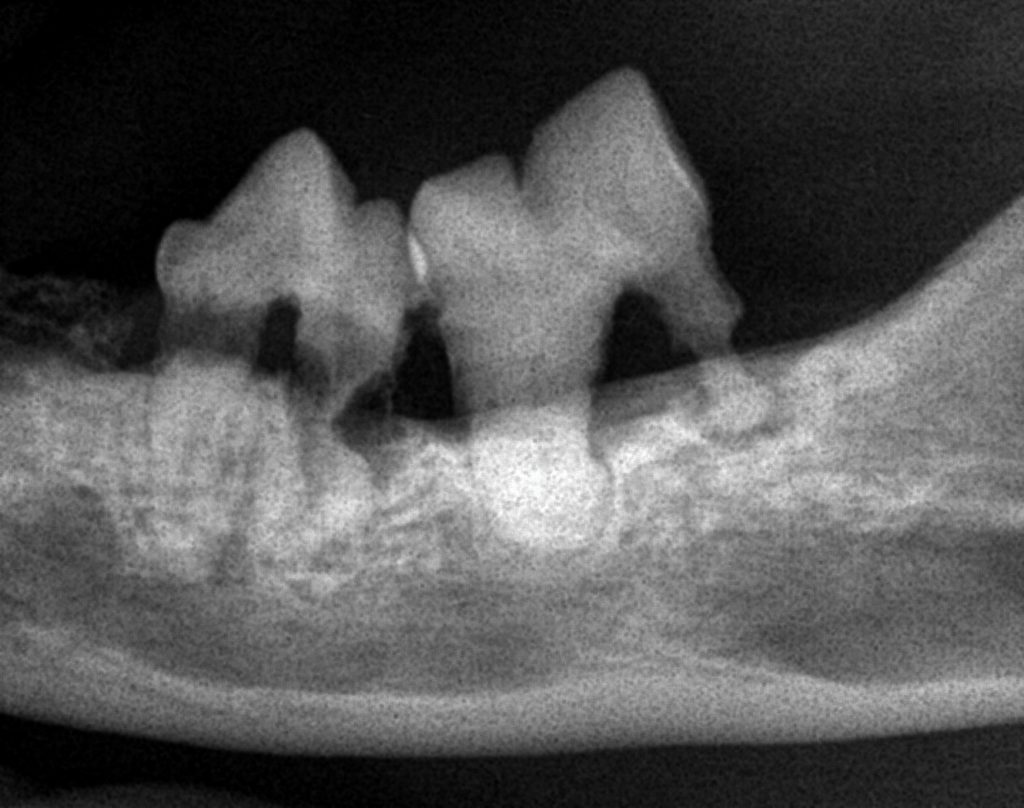

- 歯の吸収病巣(FORL)

歯科治療(抜歯)

猫の口内炎では、歯の周囲の炎症が原因となっていることが多いため、

抜歯治療

が必要になることがあります。